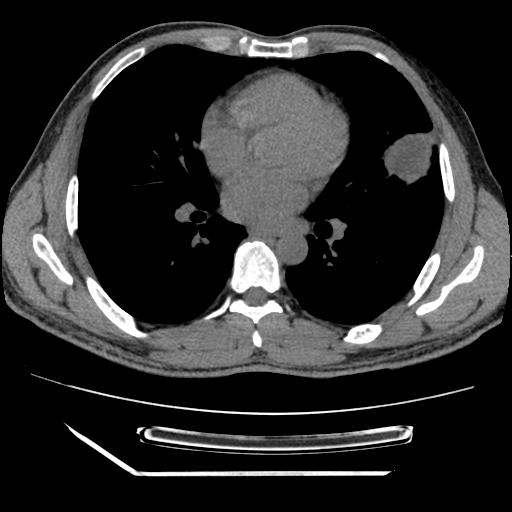

男,38岁,于2009年8月9日晚突发左侧胸痛,今x线提示左下肺阴影,为了明显确诊断,行ct检查,

血常规:嗜酸性细胞增高,单核细胞增高。

病灶发生在下叶,密度均匀,边缘模糊、毛糙,周围血管纹理增强扭曲改变,靠近胸膜处病灶胸膜反应明显。

支持考虑---球形肺炎。

左肺舌叶病变。主体病灶呈类圆形中心密度低,成液化趋势周边班片影分布

考虑肺脓肿

虽然实验室检查支持炎性病变,且病变内有坏死改变(中央呈大片状低密度影),但仍不能掉以轻心,鳞癌也可以有这种影像改变。